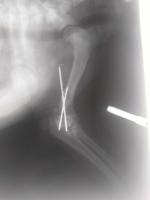

关节肘头与冠状骨斜骨折。经两个小时手术,将断骨联结